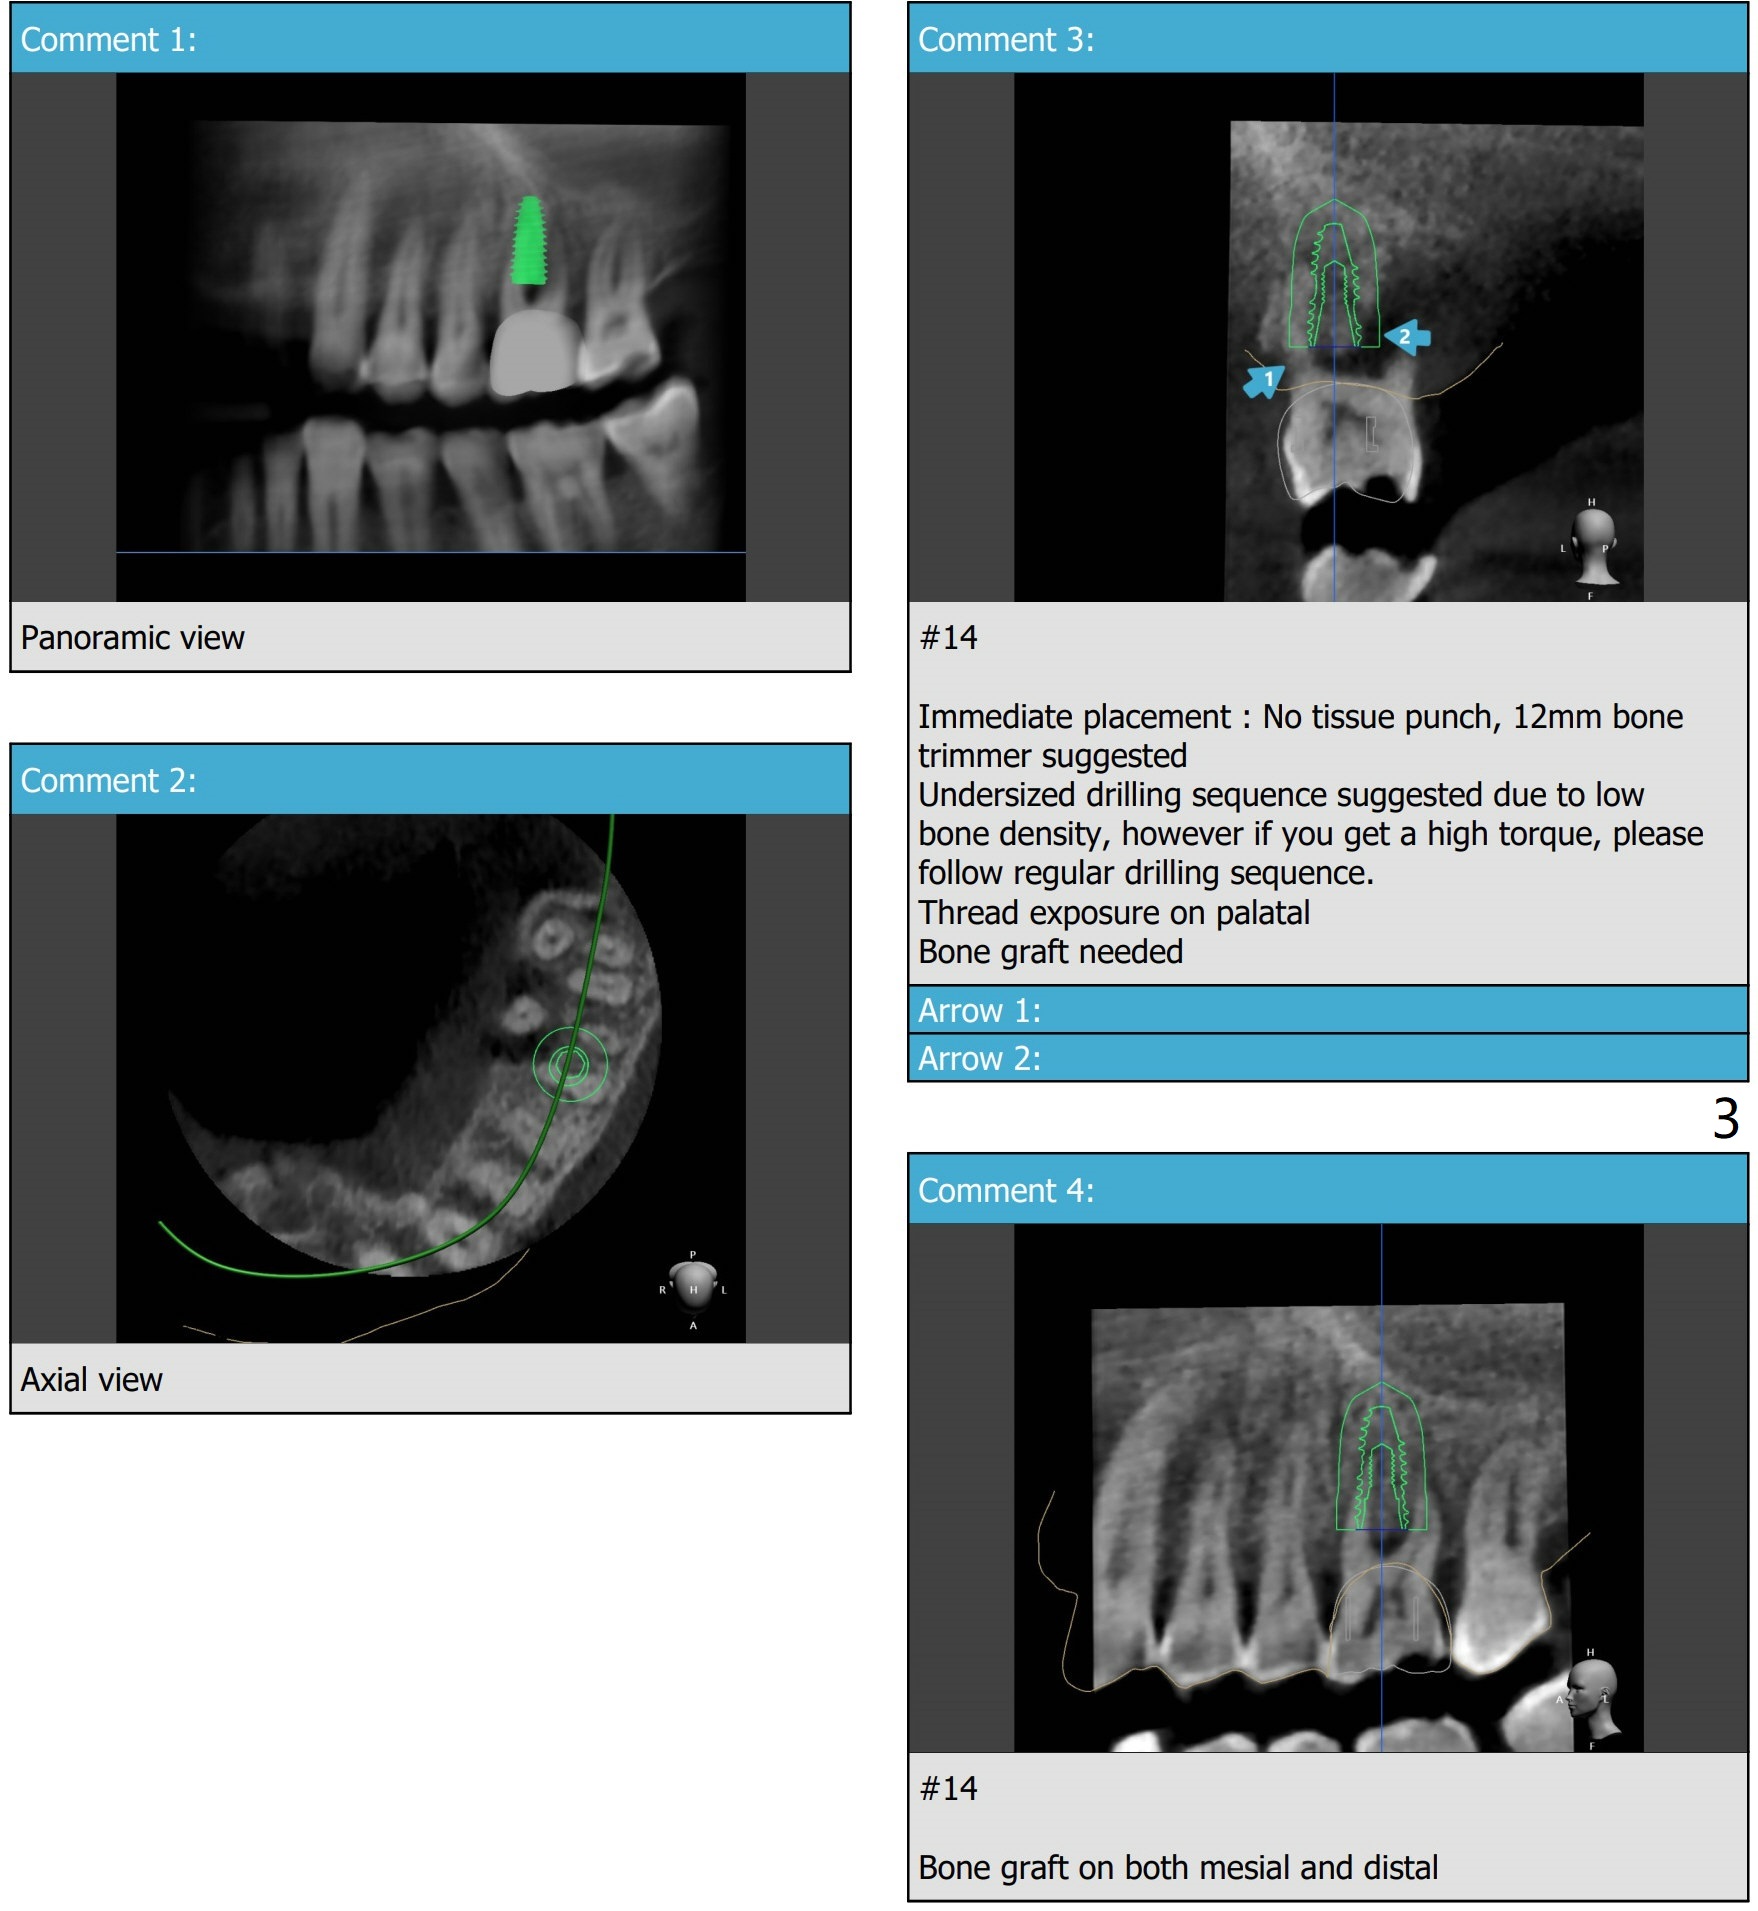

The implant is not designed to be placed in the center of the septum mesiodistally as shown in the axial section!